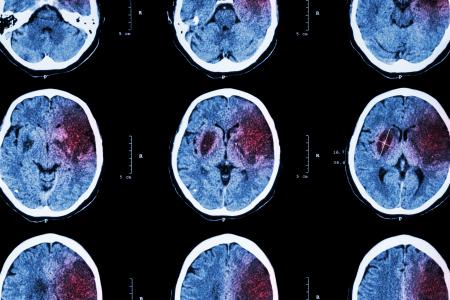

Cette recherche, menée par des neuroscientifiques de l’Université de Californie - San Francisco (UCSF) implique des facteurs connus comme l’inflammation et la santé cérébrovasculaire, et démontre, précisément les effets du stress dans la vingtaine sur les capacités cognitives à la quarantaine précisément, une neuro-inflammation plus élevée chez les jeunes adultes est liée à des performances moindres aux tests cognitifs à la quarantaine. Ces conclusions, présentées dans la revue Neurology, rappellent aussi l’impact de toutes les comorbidités de l’obésité sur la santé cérébrale et cognitive.

Cette association avait déjà été démontrée entre une inflammation plus élevée chez les personnes âgées et l’incidence de la démence, mais c’est la première recherche à relier l’inflammation au début de l’âge adulte à ce déclin cognitif à la quarantaine.

Stress, inflammation, puis déclin cognitif et démence